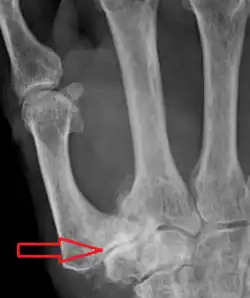

Stage 4 trapeziometacarpal osteoarthritis, with major subluxation of the joint

Stage 4:

• Narrow joint space

• Concomitant scaphotrapezial arthritis